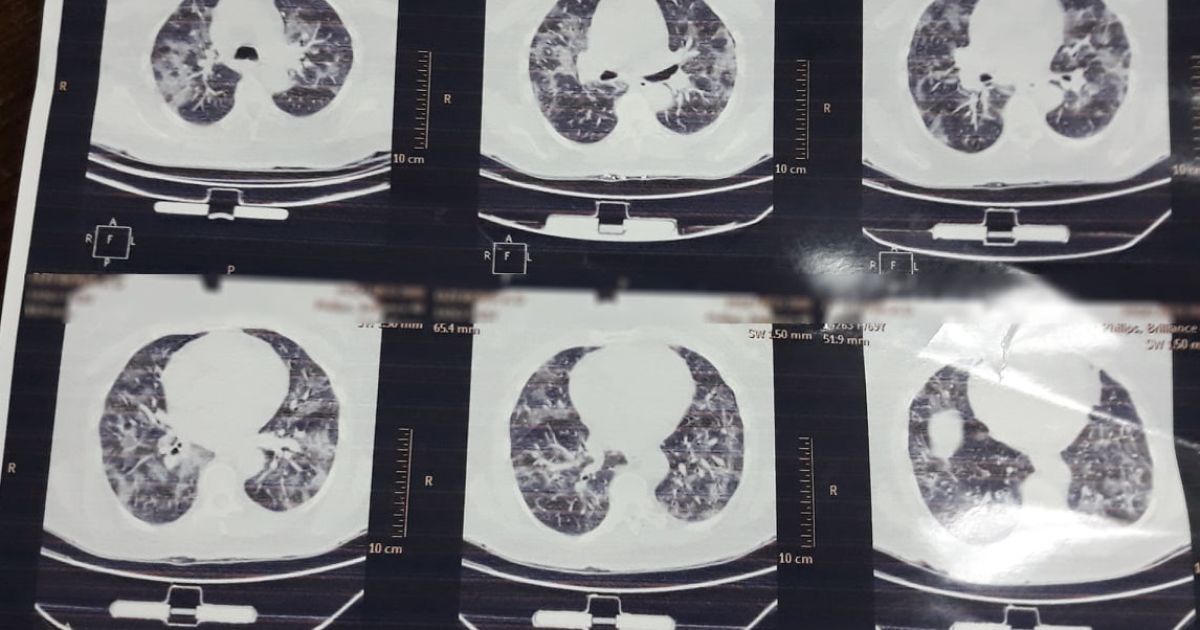

У Львові медики показали, який вигляд мають легені, уражені коронавірусом. Органи на світлині перетворилися на суцільну світлу пляму.

«Це одні з найстрашніших легенів, які я бачила в житті», – сказала мені щойно очільниця реанімації клінічної лікарні швидкої медичної допомоги Львова», – написала Ірина.

Нагадаємо, що патологоанатом розповів, як коронавірус змінює легені. Лікар говорить, що вони більше нагадують печінку.